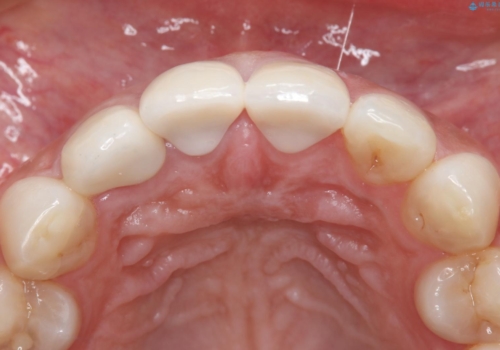

- 1週間ほど前に自転車で転倒して前歯をぶつけた後、歯の色が変わっていることが気になり受診された方です。診察の結果、失活及びエナメル質に多数の亀裂が認められたため、根管処置およびセラミッククラウンによる治療を行いました。元々右上2番目の歯の形が気になっていたとの事で、左右対称の形に近づけるように補綴しました。

左上1番目の歯は失活していませんでしたが、歯の表面に多数の亀裂が認められました。患者様のご希望により、前歯3本をまとめて補綴処置することとなりました。土台となる歯質の色が異なる状態でしたが、熟練した技工士さんの技術により3本とも同じ色味になるように仕上げていただきました。色味、形態ともに自然な被せ物に大変喜んでいただけました。